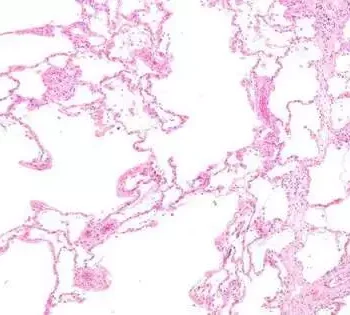

Several patients with chronic obstructive pulmonary disease (COPD) have airway-clogging mucus plugs, an accumulation of mucus in the lungs that can affect quality of life and lung function. A retrospective